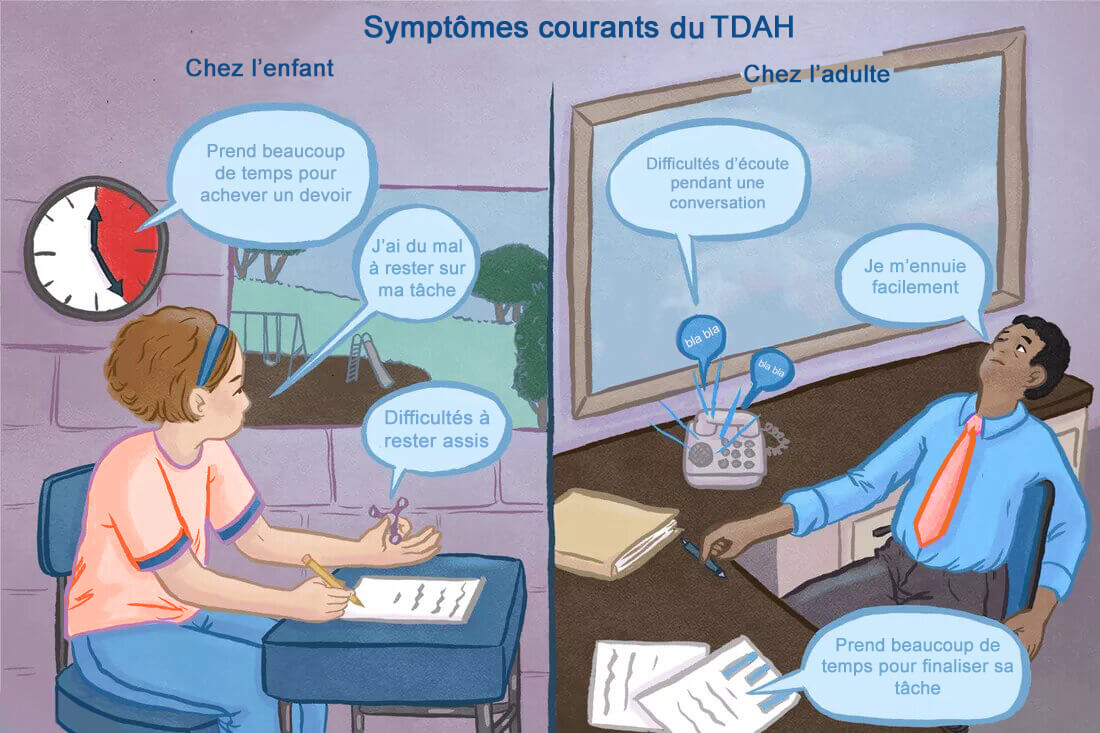

L’évolution du TDAH avec l’âge (enfant,

adolescent, adulte)

– Le trouble du déficit de l’attention chez l’adulte est souvent une continuité d’un TDAH à l’âge enfant, avec des évolutions propres à chaque personne

ÂGE ENFANT |

ÂGE ADOLESCENT |

ÂGE ADULTE |

I N A T T E N I O N |

• Fait des erreurs d’inattention • N’écoute pas les instructions • A du mal avec les devoirs du soir • Est désorganisé • Oublie souvent ses affaires |

• Difficulté à se

concentrer • A du mal avec ses devoirs du soir • S’ennuie facilement • Est désorganisé • Est facilement distrait |

• N’écoute

pas les instructions • A du mal avec la paperasse et l’administration • Oublie ses engagements • Désorganisation, mauvaise gestion du temps |

H Y P E R A C T I V I T E |

• Toujours en mouvement • Court et saute sans raisons • Tendance à faire pipi au lit • Ne sais pas s’occuper calmement |

• Se sent souvent agité et à cran • Parait occupé mais fait peu de choses • Ne sait pas s’occuper calmement • Comme conduit par un moteur |

• Nerveux • A la bougeotte avec ses membres • A du mal à rester assis longtemps • Peut parler excessivement • Jobs les plus actifs ou extraordinaires |

I M P U L S I V I T E |

• Interrompt les autres • N’écoute pas les réponses • N’attend pas son tour |

• Expérimentation de drogues • Rapports sexuels non protégés • Plusieurs partenaires sexuels • Tempérament explosif (parents, …) |

• Changements de jobs fréquents et impulsifs • Abus d’alcool, tabac, médicaments, drogues • Tempérament explosif • Accident de la route • Relation extraconjugale |